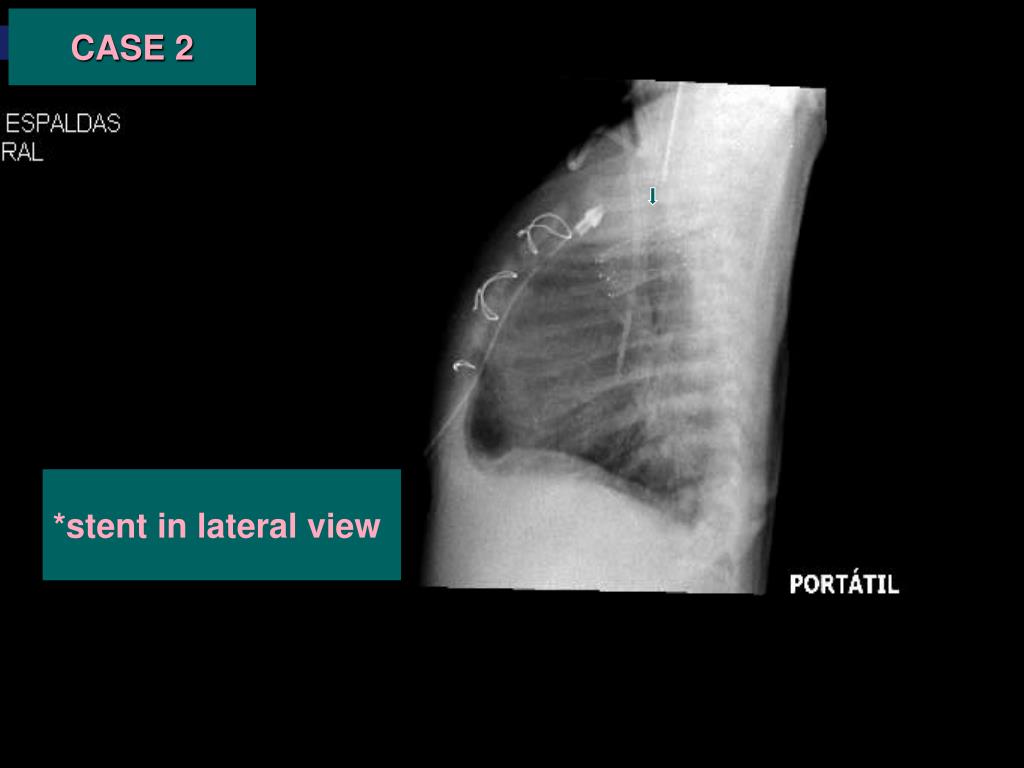

34. CASE 2 *stent in lateral view

33. ç CASE 2 *Chest X-ray: The stent is shown in the anteroposterior view